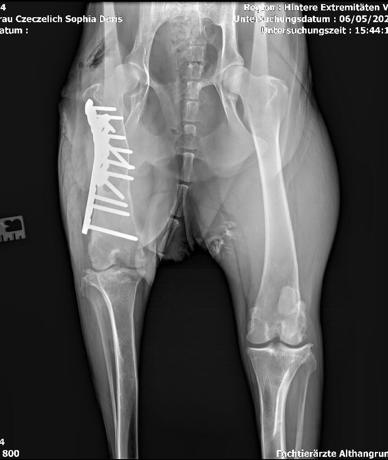

Zentralasiatischer Schäferhund | Hündin | geb. Anfang 2022 | Kastriert | Gechipt | Ausgewachsen: 58 cm und ca. 35 kg